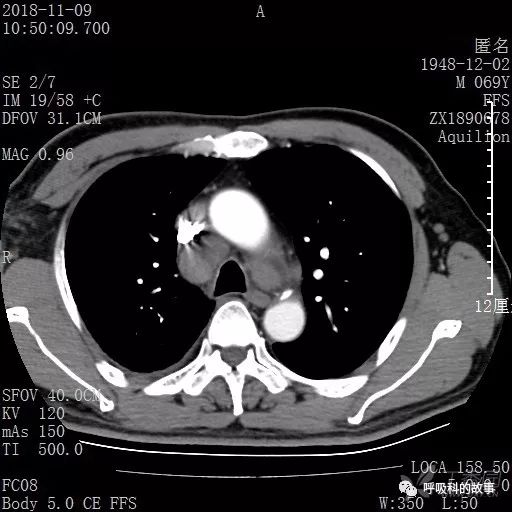

胸部增强CT示右肺门占位伴远端阻塞性肺炎,纵膈、右肺门、右侧颈根部、右侧腋下及肝门部肿大淋巴结。两侧胸腔少量积液。

纵隔窗的增强CT

患者于2018年12月初又到了另一家大医院,做了PET检查和气管镜检查,PET图片和报告:右下肺病灶在增大,PET呈现高摄取率,SUV最大达11.